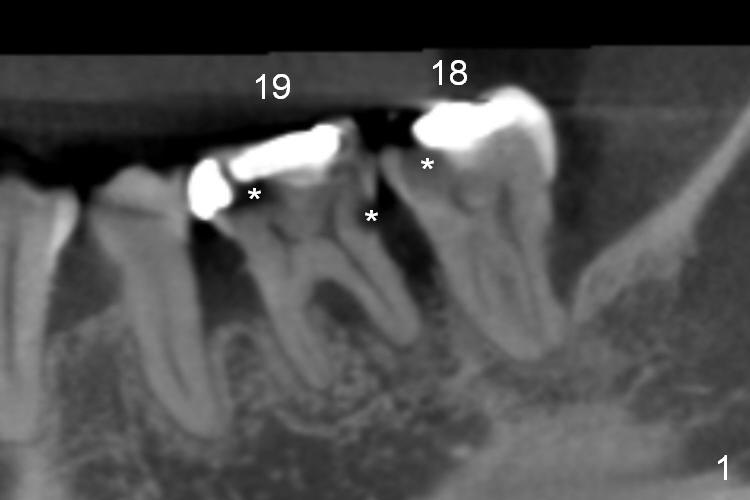

A 48-year-old lady (HJ) has several missing teeth (UL, UR, LR). Suddenly there is pain from LL quadrant, either due to caries (Fig.1 *), periodontitis or both. Conservative treatment (RCT) should be tried first. If one of the teeth is deemed non-salvageable, extraction and immediate implant is provided (Fig.2,3 (B: buccal, L: lingual)). Clindamycin will be used for socket disinfection.